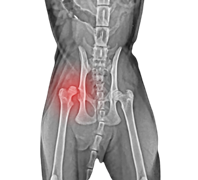

Hip dislocation surgery

สาเหตุของการเกิดข้อสะโพกเสื่อมนั้นพบว่า เกิดจากทางพันธุกรรม โภชนาการ อัตราการเจริญเติบโตของสัตว์ที่รวดเร็ว ไม่สมดุลกัน เราจึงมักพบปัญหานี้ในสุนัขพันธุ์ใหญ่ และการเลี้ยงดู

สุนัขที่มีปัญหาข้อสะโพกหลุดขึ้นอยู่กับความรุนแรงของการบาดเจ็บและวิธีการรักษาที่ได้รับ หากอาการของสุนัขไม่รุนแรงมาก และได้รับการรักษาอย่างเหมาะสม